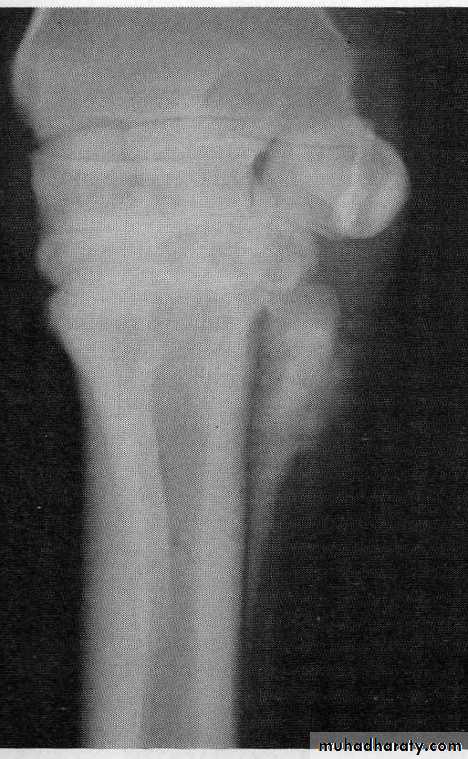

Medial Splint (arrow)

An example of a periostitis of the splint bone (arrow)Treatment:-